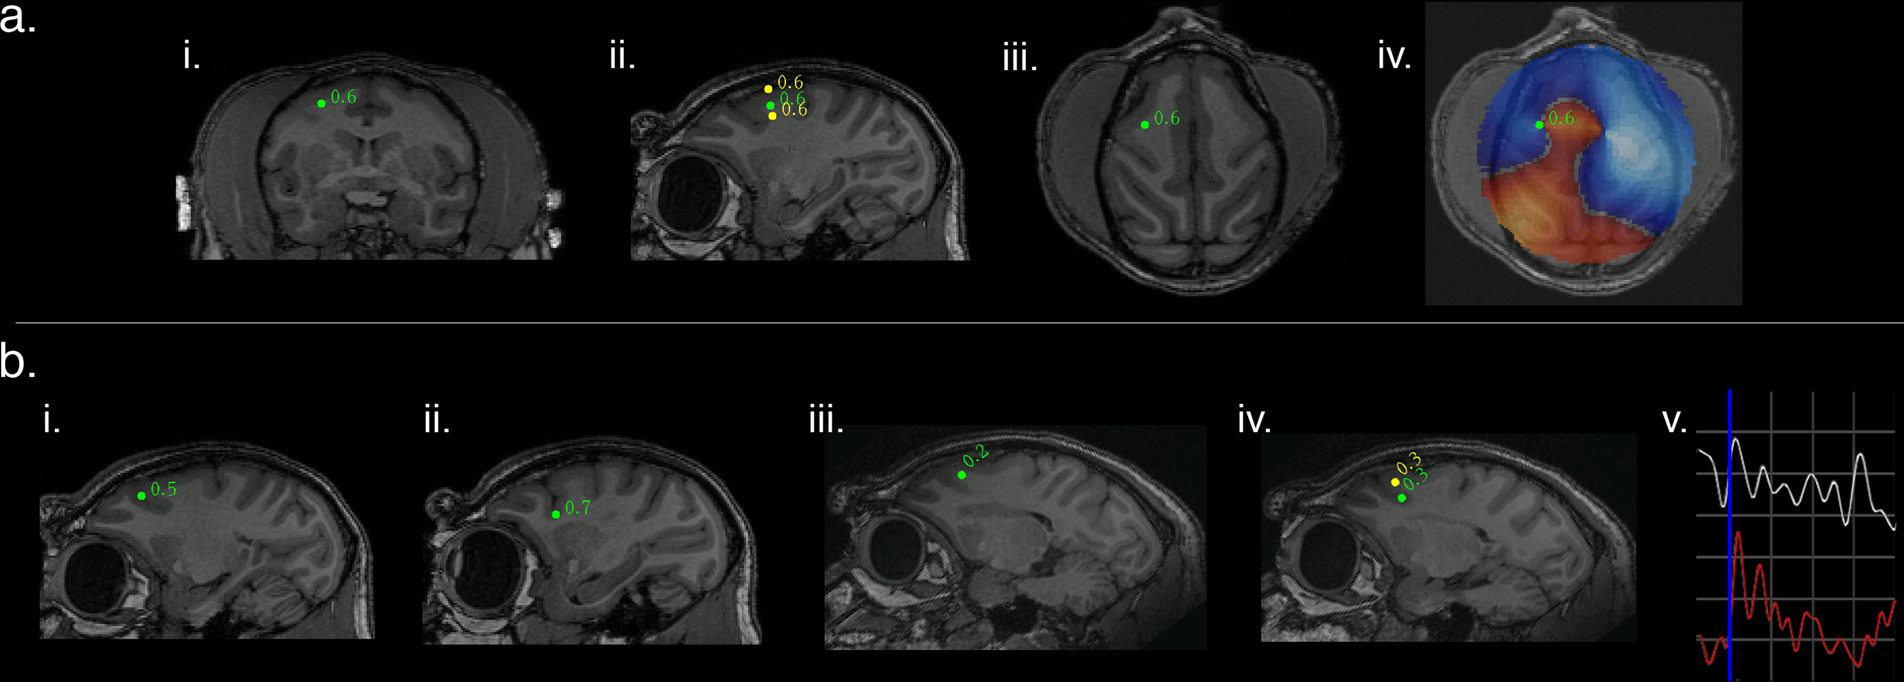

Fig. 2: SAM source localization of optogenetically evoked MEG responses in the right arcuate sulcus in two representative animals and stimulation types.

a An example of optogenetic stimulation localized by dual-state SAM to the posterior bank of right arcuate sulcus for NHP M1 in the coronal (i), sagittal (ii), and axial planes (iii), for a stimulus of 50 ms square light pulses. The whole brain, un-thresholded, dual-state SAM SPM (voxel size of 750 µm3, iv) reveals synchronized activity (red voxels) arising from the stimulation site and surrounded by desynchronization (blue voxels). Green dot and number indicate a peak in the SPM plus the associated pseudo-t value. b Right SAM arcuate peaks for four additional and different optical stimuli in two different NHPs. (bi–ii) present arcuate activations for M1 and (iii-iv) shows arcuate stimulation for M2. (bi–ii) is the same subject (M1) as presented in (ai–iv); (i) depicts the arcuate peak for 8 Hz sine waves, and (ii) shows the arcuate peak for 40 Hz sine waves. Arcuate stimulations in M2 are presented in (iii–iv); (iii) shows the arcuate peak for 10 ms square pulses and (iv) shows the arcuate peak for 20 Hz square wave pulse trains. A single trial (v) of an LFP recorded by the optrode and a simultaneous SAM virtual electrode for an arcuate peak (as seen in biii). Blue vertical line indicates stimulus onset (10 ms pulses). Both the LFP (white) and virtual electrode (red) exhibit a rapid peak following stimulation and have similar features and time courses. One gray square in the graph = 100 ms on the abscissa and for the ordinate, 35 μV for the LFP or 15 nA m for the virtual electrode. All maps follow radiological conventions.